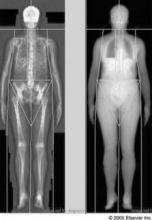

©Elsevier

A new report has offered up recommended intervals for bone mineral density screening with dual-energy x-ray absorptiometry.